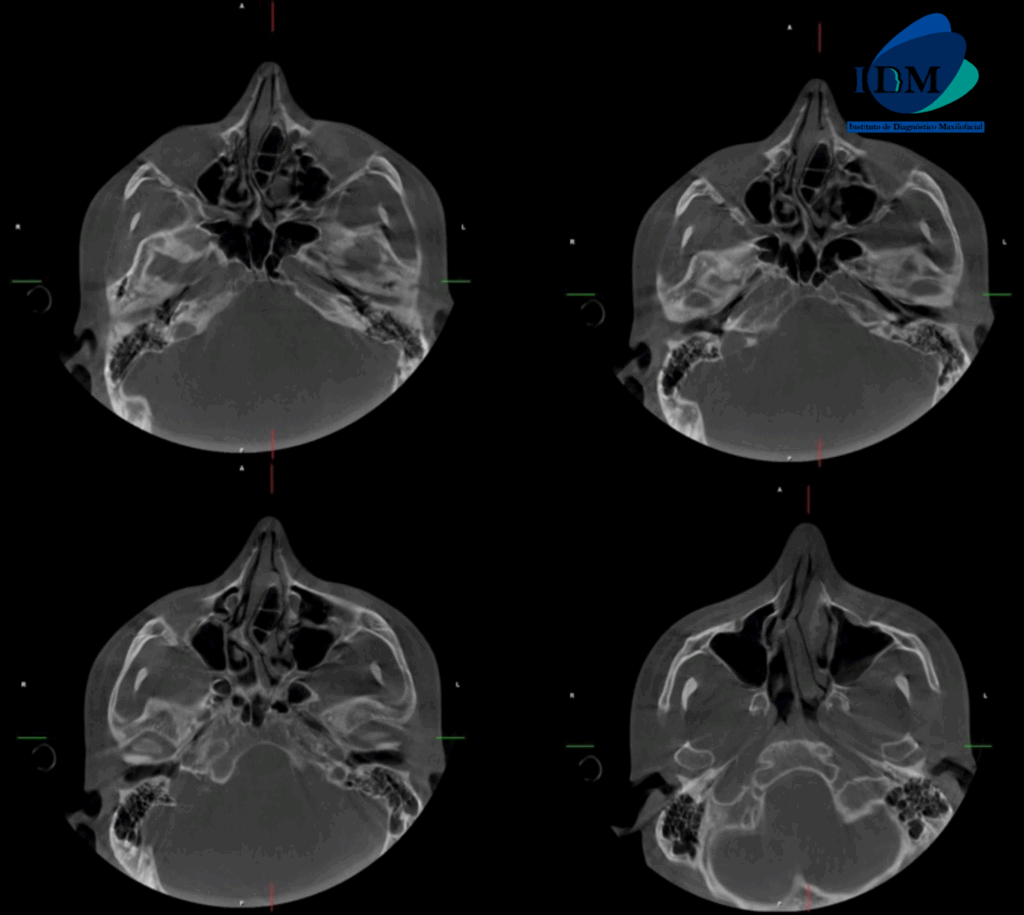

A la evaluación de la tomografía computarizada se puede observar el aumento de la longitud cefalo caudal de la apófisis coronoides bilateral que se extiende superior al borde del arco cigomático.

CORTES AXIALES